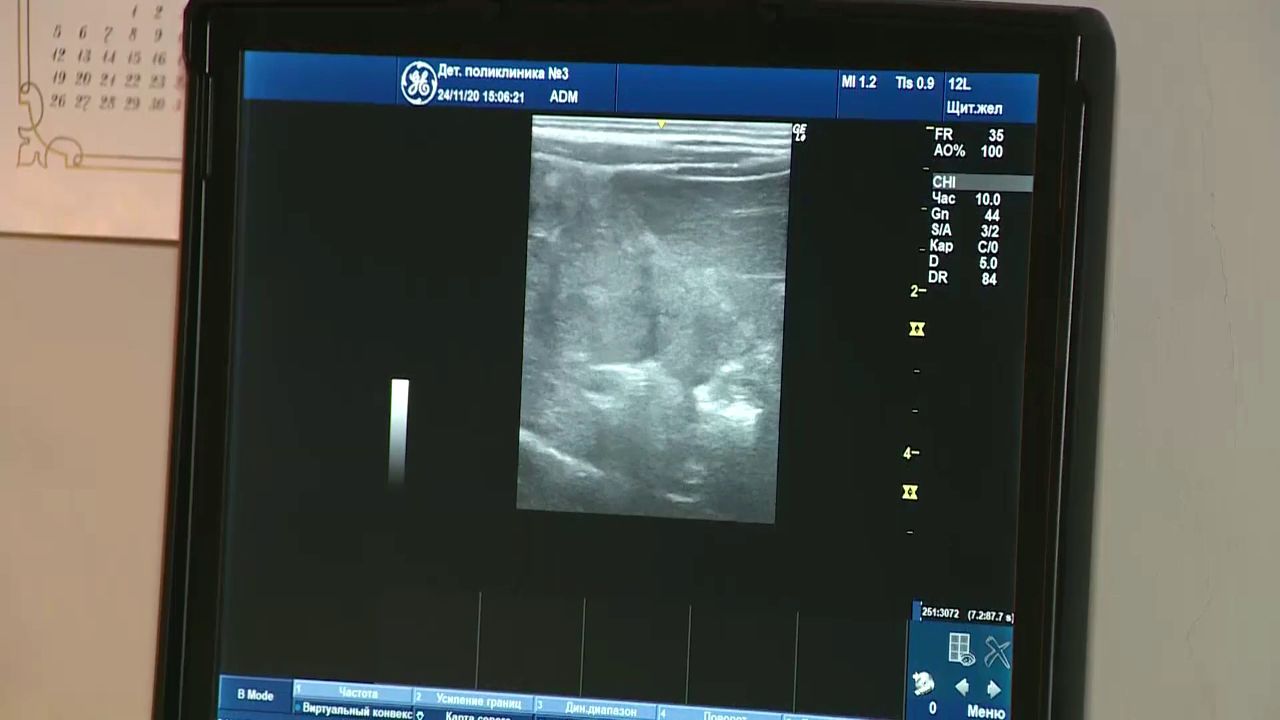

— Мы очень довольны приобретением, картинка четкая, контрастная, нас все устраивает. Мы его очень ждали, очень довольны, — поделилась врач узи-диагностики Анна Бычкова.